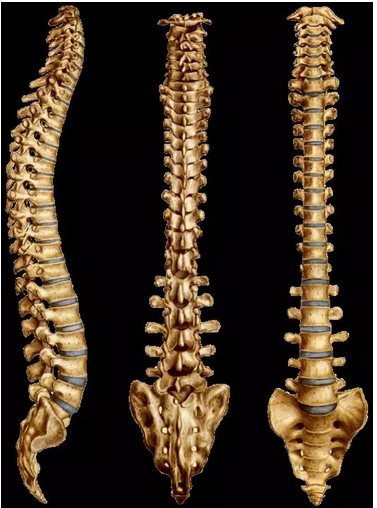

脊柱超详细图文解剖

脊柱超详细图文解剖|关节|腰椎|弓根|椎体|椎骨_网易订阅